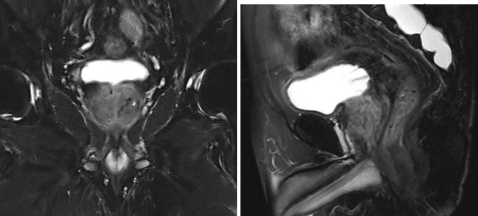

2025年6月14日,前列腺MRI示:与前片(2024年11月23日)对比前列腺体积缩小,形态欠规则,信号不均匀,治疗后改变。前列腺移行带多发结节状长T2信号影,较前减少,缩小,T2WI评分PI-RADS 2,考虑增生结节。双侧精囊腺炎,较前相仿。原膀胱导尿管留置,现已取出。膀胱炎可能,较前改善。盆腔少量积液,较前基本吸收。骶管囊肿,较前相仿。

图4 2025年6月14日MRI检查

2025年12月11日,TPSA<0.008ng/mL。前列腺MRI示:与前片(2025年6月12日)对比前列腺形态欠规则,信号不均匀,大致同前,可符合治疗后改变,请结合临床。双侧精囊腺炎,较前相仿。膀胱炎可能,大致同前。盆腔小淋巴结可见,大致同前。骶管囊肿,较前相仿。